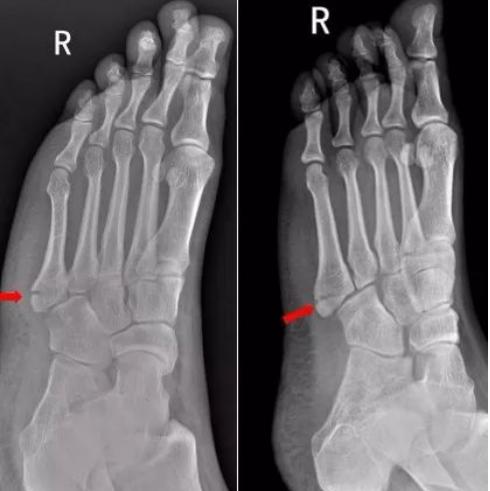

1、患者下楼梯,左脚踩空,左脚外侧扭伤来院就诊,拍片如下:

右足第5跖骨基底部见骨折线,断处稍分离移位,右足第5跖骨基底部骨折